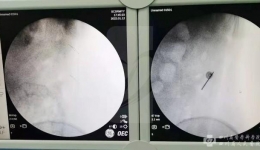

• 在C型臂X光机的帮助下采用微创腹腔镜手术顺利为患者取出绣花针

在C型臂X光机的帮助下采用微创腹腔镜手术顺利为患者取出绣花针

前段时间,我们门诊收治了一例特殊的患者。入院前,他在当地医院做脊柱椎间盘手术时,常规腹部照片发现左上腹部有3CM*1MM条形高密度影,怀疑金属状物。反复追问病史,患者和家属都否认外伤及手术史,体格检查也没发现身体有明显伤道和手术瘢痕残留...